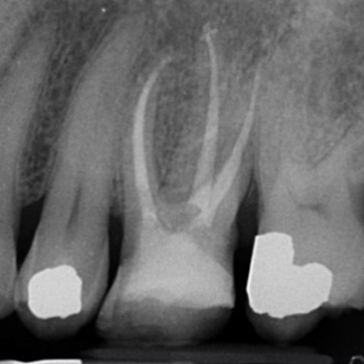

Case 1. Re-RCT of LL6